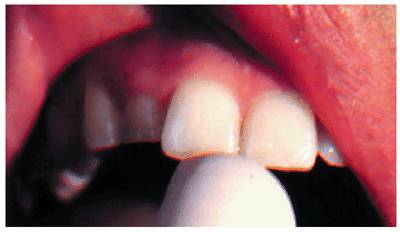

Figure 19-1A: Transillumination of a maxillary left central incisor with a necrotic pulp.

Figure 19-1B: Transillumination of the adjacent tooth with a vital pulp. Because there is active blood flow through the live pulp tissue, the tooth appears brighter to the fiber-optic light than the adjacent tooth with a necrotic pulp.

Transillumination via a fiber-optic light may be of great assistance in

detecting color shifts in a crown (Figures 19-1A, and 19-1B). A tooth with a pink or reddish

hue would more than likely indicate internal hemorrhage from a recent injury (Figure 19-2), a dental procedure (Figure 19-3), or gingival tissue hyperplasia